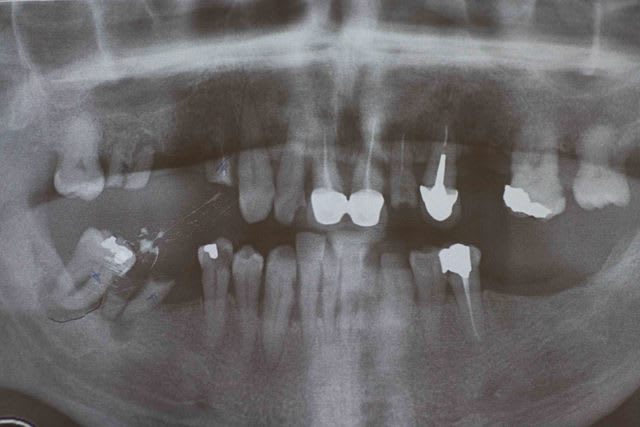

J'avais oublié la pano de départ + la photo des fraisages et attachement .

Sur la pano, les ant. inf semble très faible

(paro, perte osseuse, extrusion)

Tu as prévu quoi ?